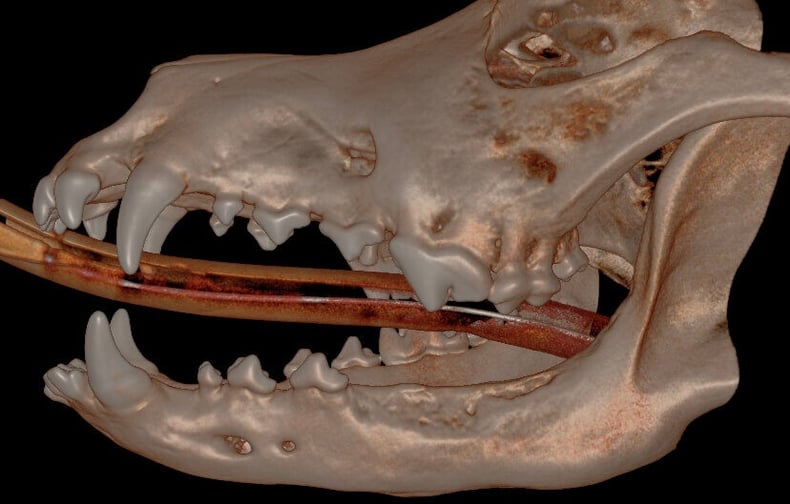

Below: 3D Hard Tissue Overview (left side)

.jpg?width=790&height=486&name=3D%20Hard%20Tissue%20Overview%20(left%20side).jpg)